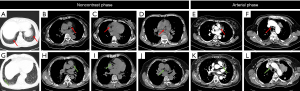

Group 1 demonstrated significantly fewer motion artifacts in the lung (P=0.027) and mediastinum (P<0.001) than did Group 2 (Table 2 and Figure 2). Although no statistical difference was observed in overall image scores, they were consistently higher in abdomen in Group 1 than in Group 2 (Figure 3). Comparable results were found for pelvic image quality, image noise, organ enhancement, and lesion conspicuity (P>0.05; Figure 4). The percentage of images with significant motion artifacts in mediastinum was significantly lower in Group 1 than in Group 2 (Reader 1: 1.2% vs. 30.6%; Reader 2: 2.4% vs. 32.9%; P<0.001; Table 3). No statistically significant differences were observed in the severity distribution of artifacts between the lung, abdomen, and pelvis in Group 1. The intraobserver (κ=0.788–0.964) and interobserver agreement (κ=0.708–0.929) in the subjective image quality analysis was good to excellent.

Poor breath-holding or an inability to breath-hold for the scanning of areas susceptible to movement can cause serious motion artifacts, which has limited value in diagnosis (28). High-pitch DSCT makes free-breathing scans possible while preserving image quality (15,29). Our results showed that high-pitch DSCT led to fewer motion artifacts in the lung and mediastinum and resulted in a higher chest SNR and CNR. However, increased pitch has been reported to increase image noise and decrease SNR, consequently reducing objective image quality in CT scans acquired under constant tube current conditions (30). A previous study found that high-pitch DSCT had inferior results for image noise and SNR compared to standard-pitch single-source CT (SSCT) when both used filtered back-projection (FBP) reconstruction. However, image reconstruction via ADMIRE increased objective image quality in high-pitch DSCT as compared to the standard-pitch SSCT level (which utilized FBP) (4). We used the same ADMIRE image reconstruction algorithm in the two groups, which precluded its contribution to the observed differences in results. Although modern CT automatic exposure control (AEC) systems generally maintain consistent noise levels across pitch settings by modulating tube current (31), our trachea-specific ROI measurements revealed statistically significant lower noise in high-pitch acquisitions (P<0.001; Table 4). This localized noise reduction, facilitated by AEC compensation for per-rotation dose differences, likely explains the concurrent higher SNRs and lower radiation dose in the high-pitch group, even in minimally motile regions. In addition, we had excellent image quality in terms of cardiovascular structures (Figure 2H-2I,2K). As is widely known, coronary artery evaluation is usually not available in conventional nongated chest imaging because of the pulsation of heart and blood vessels. However, cardiovascular structures often appear with high quality on nongated routine chest imaging under a high-pitch protocol, providing a valuable opportunity for the diagnosis of clinically undetected cardiovascular diseases (32). Studies based on high-pitch protocols have documented nearly completely suppressed respiratory motion artifacts and cardiac pulsation artifacts on chest CT (29,33).